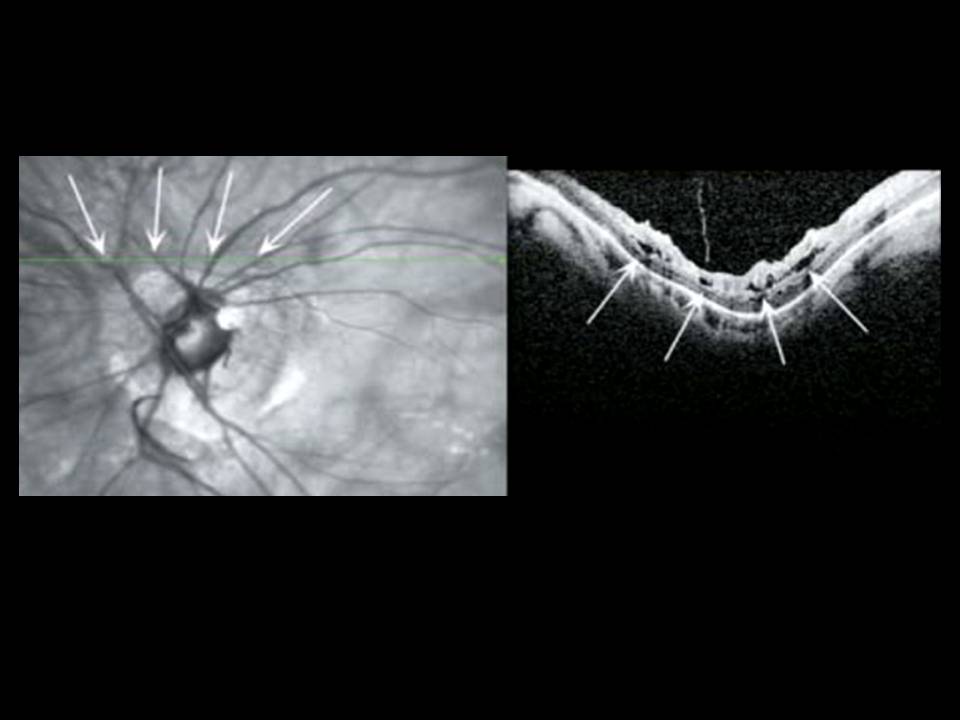

A miopia patológica é uma causa importante de cegueira, com prevalência crescente nos países desenvolvidos e em idades progressivamente mais jovens. É-lhe tradicionalmente atribuída uma forte componente genética, reconhecendo-se hoje fatores ambientais que podem limitar a sua progressão. Embora em muitos casos o agravamento da acuidade visual fosse atribuído à presença de neovascularização coroideia, descolamento de retina ou desenvolvimento de buraco macular, noutros esta progressão permanece por explicar. Novas técnicas de tomografia por coerência óptica permitiram recentemente a descoberta de entidades patológicas relacionadas com a maculopatia miópica, que abrem portas ao avanço na compreensão fisiopatológica da doença e na sua abordagem terapêutica, particularmente cirúrgica. Salientam-se os fenómenos de foveosquisis miópica, cavitação intracoroideia, tração vítrea paravascular (com formação de quistos, micropregas e defeitos lamelares) e fenómenos de distorção macular que revemos neste trabalho.